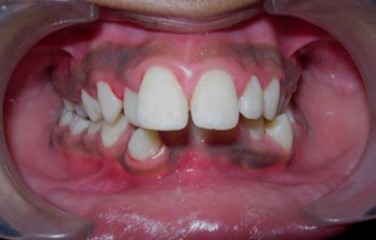

Intraoral assessment. (Figure 1d,Figure 1e,Figure 1f,Figure 1g,Figure 1h).

The maxillary arch was V-shaped with severely proclined and rotated maxillary incisors with a palatally placed 12. The mandibular arch was U-shaped with severe crowding of mandibular incisors, with 43 partially erupted and buccally placed with transpositioned 42 and 43, with 42 mesiolingually rotated, 33 distolingually rotated and 34 distolingually rotated and buccally placed.

Severe increase in overjet and deep bite were both observed. The maxillary midline coincided with the skeletal midline but the mandibular midline was shifted to the right side by 1 mm. Bilateral maxillary posterior crossbite was also observed. On right side the molar relation was Class I and on the left side it was Class II. The canine relation was Class II on the left side and the curve of Spee was increased.